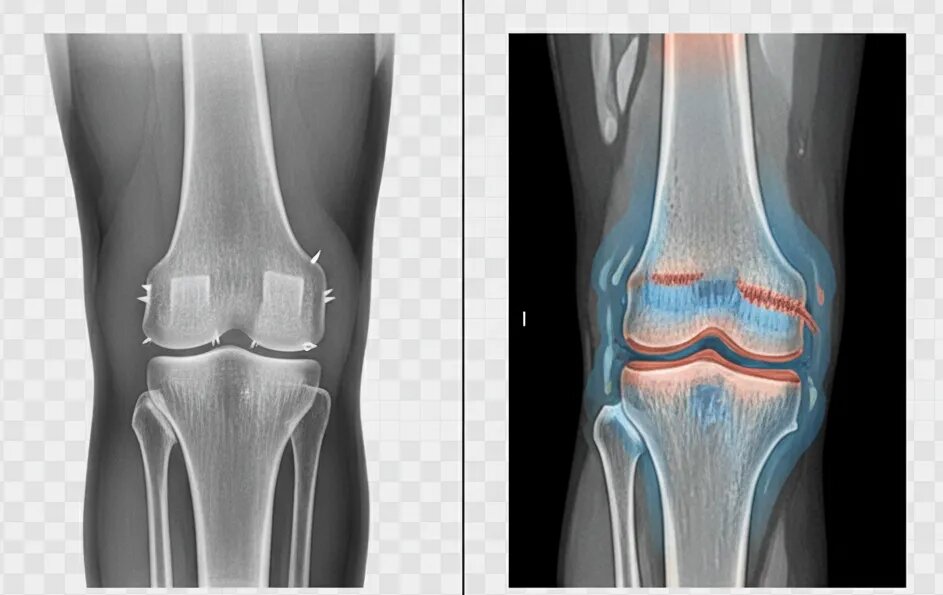

Остеоартрит является наиболее распространённой причиной хруста в коленях, особенно у пожилых людей. Состояние характеризуется дегенерацией хряща и изменениями в структуре сустава, что может приводить к трению костей и хрусту.

Повреждения менисков, хрящей или связок также могут вызывать хруст, особенно при движении колена. В таких случаях хруст часто сопровождается болью, отёками и ограничением подвижности.

При наличии хруста и боли в колене следует провести рентгенографию и, при необходимости, МРТ для оценки состояния хрящевой ткани и структуры сустава.

Диагноз остеоартрита подтверждается при наличии рентгенологических признаков, таких как сужение суставной щели и остеофиты (костные разрастания).